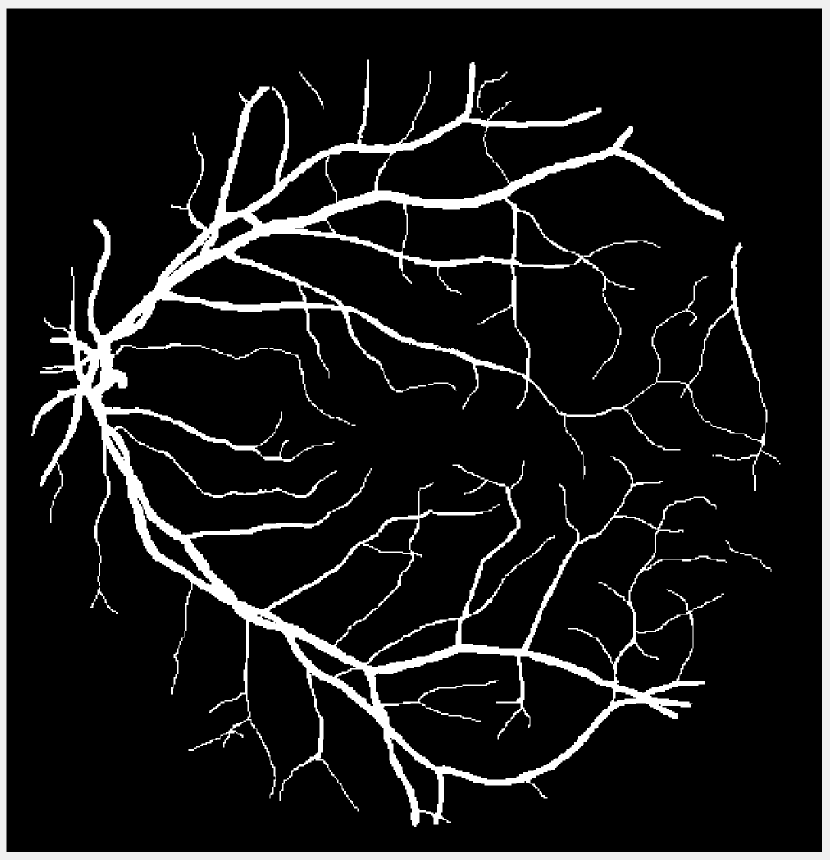

(a) Vessel 1

(b) Vessel 2

(c) Vessel 3

Figure 1: Original images for testing. (a)-(c) Retinal vessel images from the DRIVE dataset [23]. Image size is 584×565584565584\times 565 with pixel intensities 191 (vessel) and 104 (background). (d)-(g) Brain images from the BrainWeb dataset [24]. Image size is 104×8710487104\times 87 with pixel intensities 10 (background), 48 (cerebrospinal fluid), 106 (grey matter), and 154 (white matter).

We compare the performance of the proposed TTV-regularized image segmentation model with its counterparts regularized by (isotropic) TV [8], TVp [12], and AITV [15]. The algorithm we use for TV is similar to Algorithm 1 in that we use the 2,1subscript21\ell_{2,1} proximal operator in (7). For TVp, we use the ADMM algorithm following [12] but without the bias term for fair comparison and set p=1/3𝑝13p=1/3 as suggested. For AITV, we use the difference-of-convex algorithm (DCA) [25] designed in [15] and set α=0.5𝛼0.5\alpha=0.5 as suggested. The image segmentation models are applied to the images shown in Figure 1. For Figures 1(a)-1(c), we perform binary segmentation to identify the retina vessels, while for Figures 1(d)-1(g), we perform multiphase segmentation (N=4𝑁4N=4) to identify the cerebrospinal fluid (CSF), grey matter (GM), and white matter (WM) separate from the background. We evaluate the segmentation performance by two metrics: DICE index [26] and Jaccard similarity index [27]. The parameters for each segmentation method are carefully tuned so that we obtain the best DICE indices. Specifically, for Algorithm 1 that solves (4), we set β1=β2=0.25subscript𝛽1subscript𝛽20.25\beta_{1}=\beta_{2}=0.25 and find the optimal parameter λ𝜆\lambda in the range [0.0025,0.05]0.00250.05[0.0025,0.05] for both binary and multiphase segmentation. For binary segmentation, we select the best value for a{5,10,100}𝑎510100a\in\{5,10,100\} while for multiphase segmentation, we select for a{1,5,10}𝑎1510a\in\{1,5,10\}. Algorithm 1 is initialized with the results of fuzzy c𝑐c-means clustering [28] and it terminates either when UtUt1FUtF<104subscriptnormsuperscript𝑈𝑡superscript𝑈𝑡1𝐹subscriptnormsuperscript𝑈𝑡𝐹superscript104\frac{\|U^{t}-U^{t-1}\|_{F}}{\|U^{t}\|_{F}}<10^{-4} or after 200 iterations. The experiments are performed in MATLAB R2022b on a Dell laptop with a 1.80 GHz Intel Core i7-8565U processor and 16.0 GB of RAM. The code for Algorithm 1 is available at https://github.com/JimTheBarbarian/Official-TTV-Segmentation.

Before applying the segmentation algorithms, the images in Figure 1 are normalized to [0,1]01[0,1] followed by Gaussian noise corruption. The retina vessel images are corrupted with Gaussian noise of mean 0 and variance 0.01. Table I reports the performances and times of the segmentation methods on the retina vessel images while Figure 2 shows some of their results. TTV (a=10,100)𝑎10100(a=10,100) has the highest DICE and Jaccard similarity indices across the three images although requiring about 80 seconds to complete, thereby being slower than TV and TVp. The brain images are corrupted with Gaussian noise of mean 0 and variance 0.04. Table II reports the performances and times of the multiphase segmentation, while Figure 3 shows the segmentation results of Figure 1(g). By its DICE and Jaccard similarity indices, TTV (a=1)𝑎1(a=1) is best at segmenting CSF across the four images while TTV (a=5,10)𝑎510(a=5,10) remains competitive against AITV in segmenting GM and WM. On average, TTV (a=1,5)𝑎15(a=1,5) is among the top two best-performing methods. Although it can be outperformed by AITV, it is at least three times faster. In Figure 3, we see that TTV (a=5)𝑎5(a=5) is most effective in segmenting CSF, especially compared to TV and TVp. Moreover, comparable to TV and AITV, it is able to identify most of the GM and WM regions. Overall, using TTV, the proposed method is able to effectively identify narrow, thin regions such as the retina vessels and CSF.